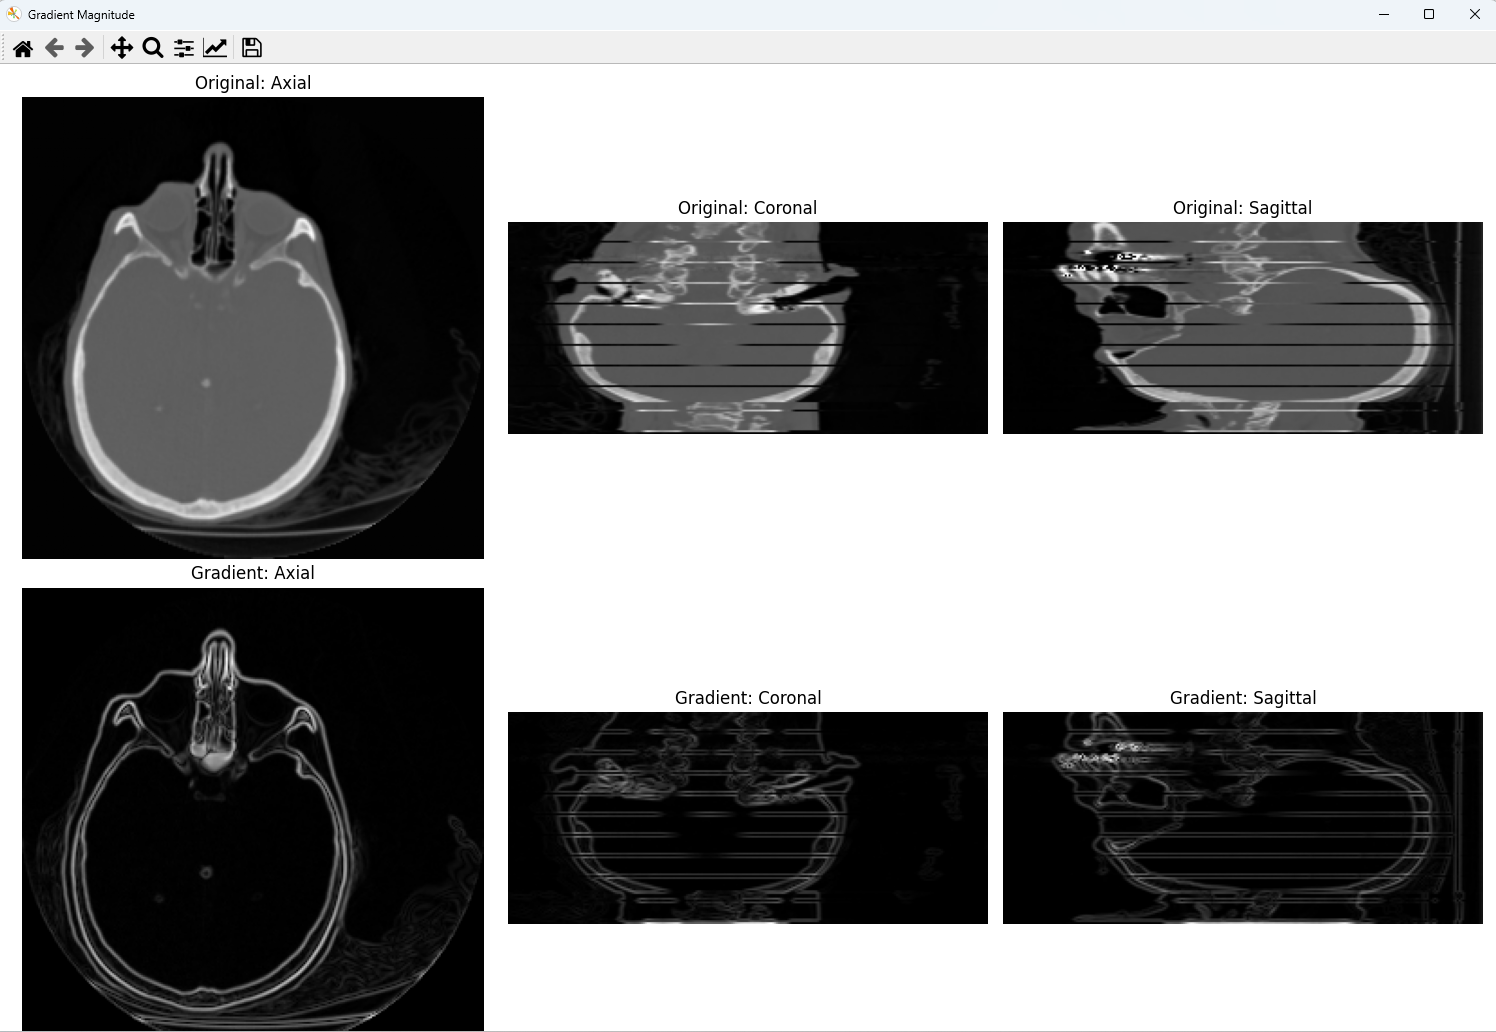

勾配は、各点における輝度値の変化率を表すベクトルである。3次元データでは、x・y・z各軸方向の偏微分を計算し、その大きさ(magnitude)を求めることで、輝度変化の激しさを可視化できる。

上段に元画像、下段に勾配の大きさを表示する。元画像では組織全体が見えるのに対し、勾配画像では境界のみが白く浮かび上がる。